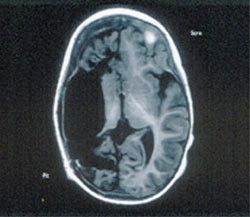

1. Hemispherectomy

Surprisingly, this surgical technique entails the removal or deactivation of one entire brain hemisphere. It is primarily employed to address severe seizure disorders where epilepsy originates in a widespread area of one brain hemisphere and cannot be controlled with medication. First performed on a human in 1923 by Walter Dandy, this procedure results in partial or complete paralysis on the side of the body opposite the removed hemisphere. Over time, neurons from the remaining hemisphere often compensate by forming new connections to assume the functions of the lost hemisphere.